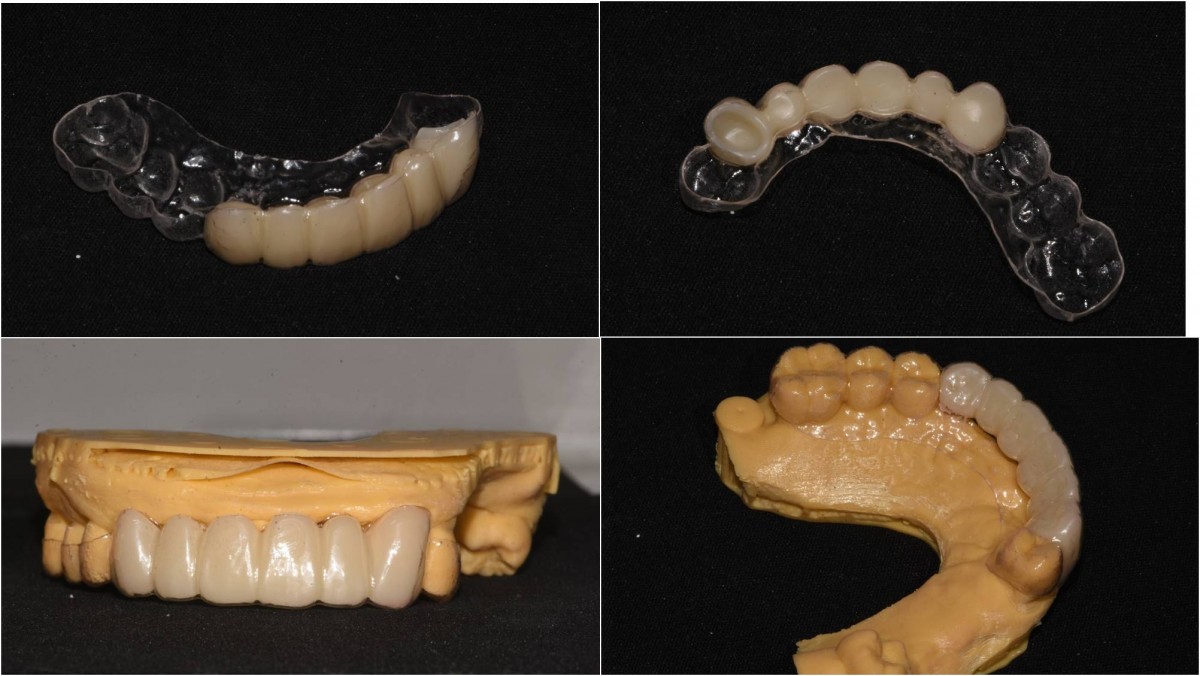

In the anterior maxilla, implant-supported fixed partial denture.

<GCpbc> A 58-year-old male is a patient undergoing implant installation in various parts. The old Br of the anterior maxilla has fallen

off and it is no longer possible to maintain it even temporarily, so a

treatment plan for the anterior teeth was made.